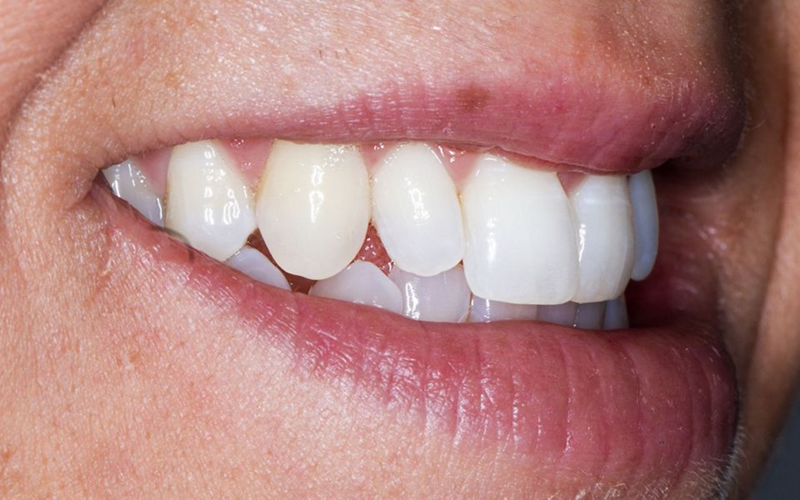

口外检查中,面部评价显示面部对称、比例匀称。微笑分析显示中线矢状面与微笑中线重合,上切牙和尖牙的暴露率为90%(图1)。微笑还显示侧切牙形状不同,与对侧恒尖牙相比,左上乳尖牙更短、更窄、颜色更黄(图2-4)。

Fig. 3: Right lateral view of the patient’s smile.